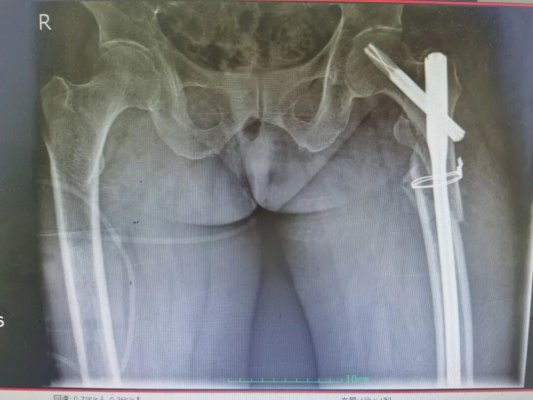

90岁的慕奶奶(化名)在家中不慎摔倒,当即出现左髋部剧痛、无法活动的情况,被紧急送至青岛西海岸第二医院就诊,经检查确诊为左侧股骨粗隆下粉碎性骨折,这正是让老年患者闻之色变的 “人生最后一次骨折”。

(术前影像)

而骨折只是冰山一角,慕奶奶(化名)的身体还藏着多重致命隐患:重度骨质疏松、高血压、心肌梗死支架术后、慢性心力衰竭,还伴有失血性贫血(术前血红蛋白仅 90g/L)、肥胖合并严重低蛋白血症(白蛋白仅 30g/L),术前超声发现其存在双侧下肢深静脉血栓,血栓随时可能脱落引发致死性肺栓塞,低蛋白血症让伤口愈合能力极差、感染风险飙升,心力衰竭则让输血、输液都面临着循环超负荷的致命风险,11 项诊断让整个救治工作如履薄冰。